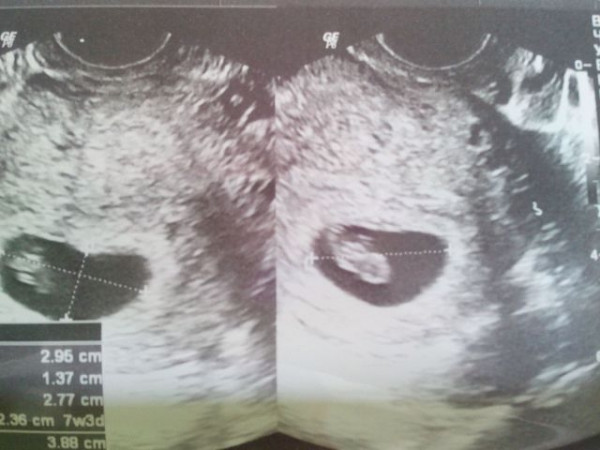

Фото Узи 8 Недель